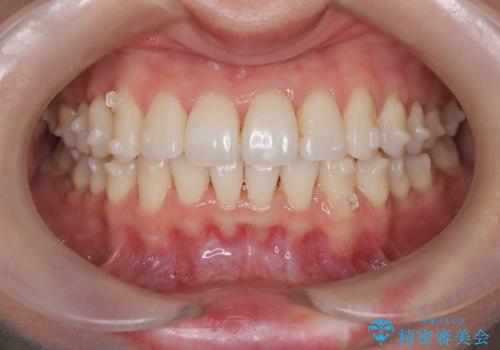

- 患者様は、**前歯の叢生(がたつき)**を気にされて来院されました。

できるだけ歯を削らずに、自然な歯並びを手に入れたいというご希望がありました。

診査の結果、中等度の叢生であったため、インビザラインモデレートでの対応が可能と判断しました。

歯へのダメージを抑えるため、IPR(歯間削合)は必要最小限にとどめる方針としました。